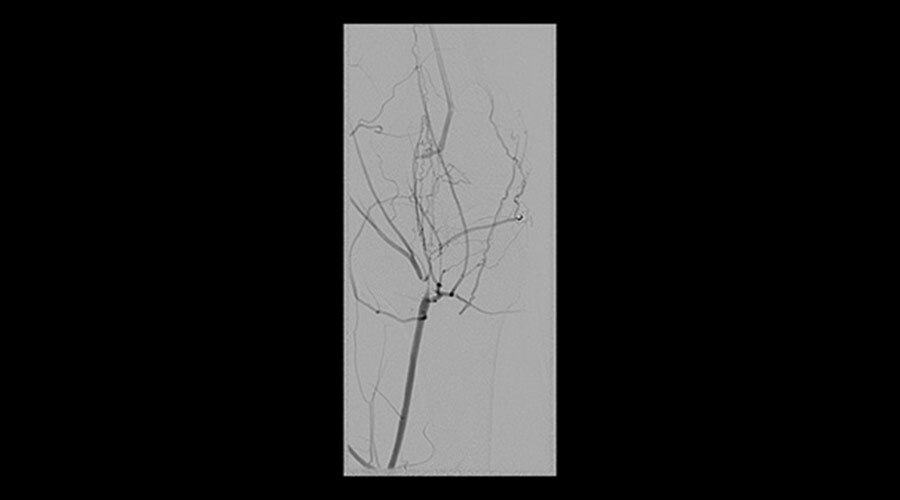

Klinik Görüntüler

-

İliyak stentlemesi